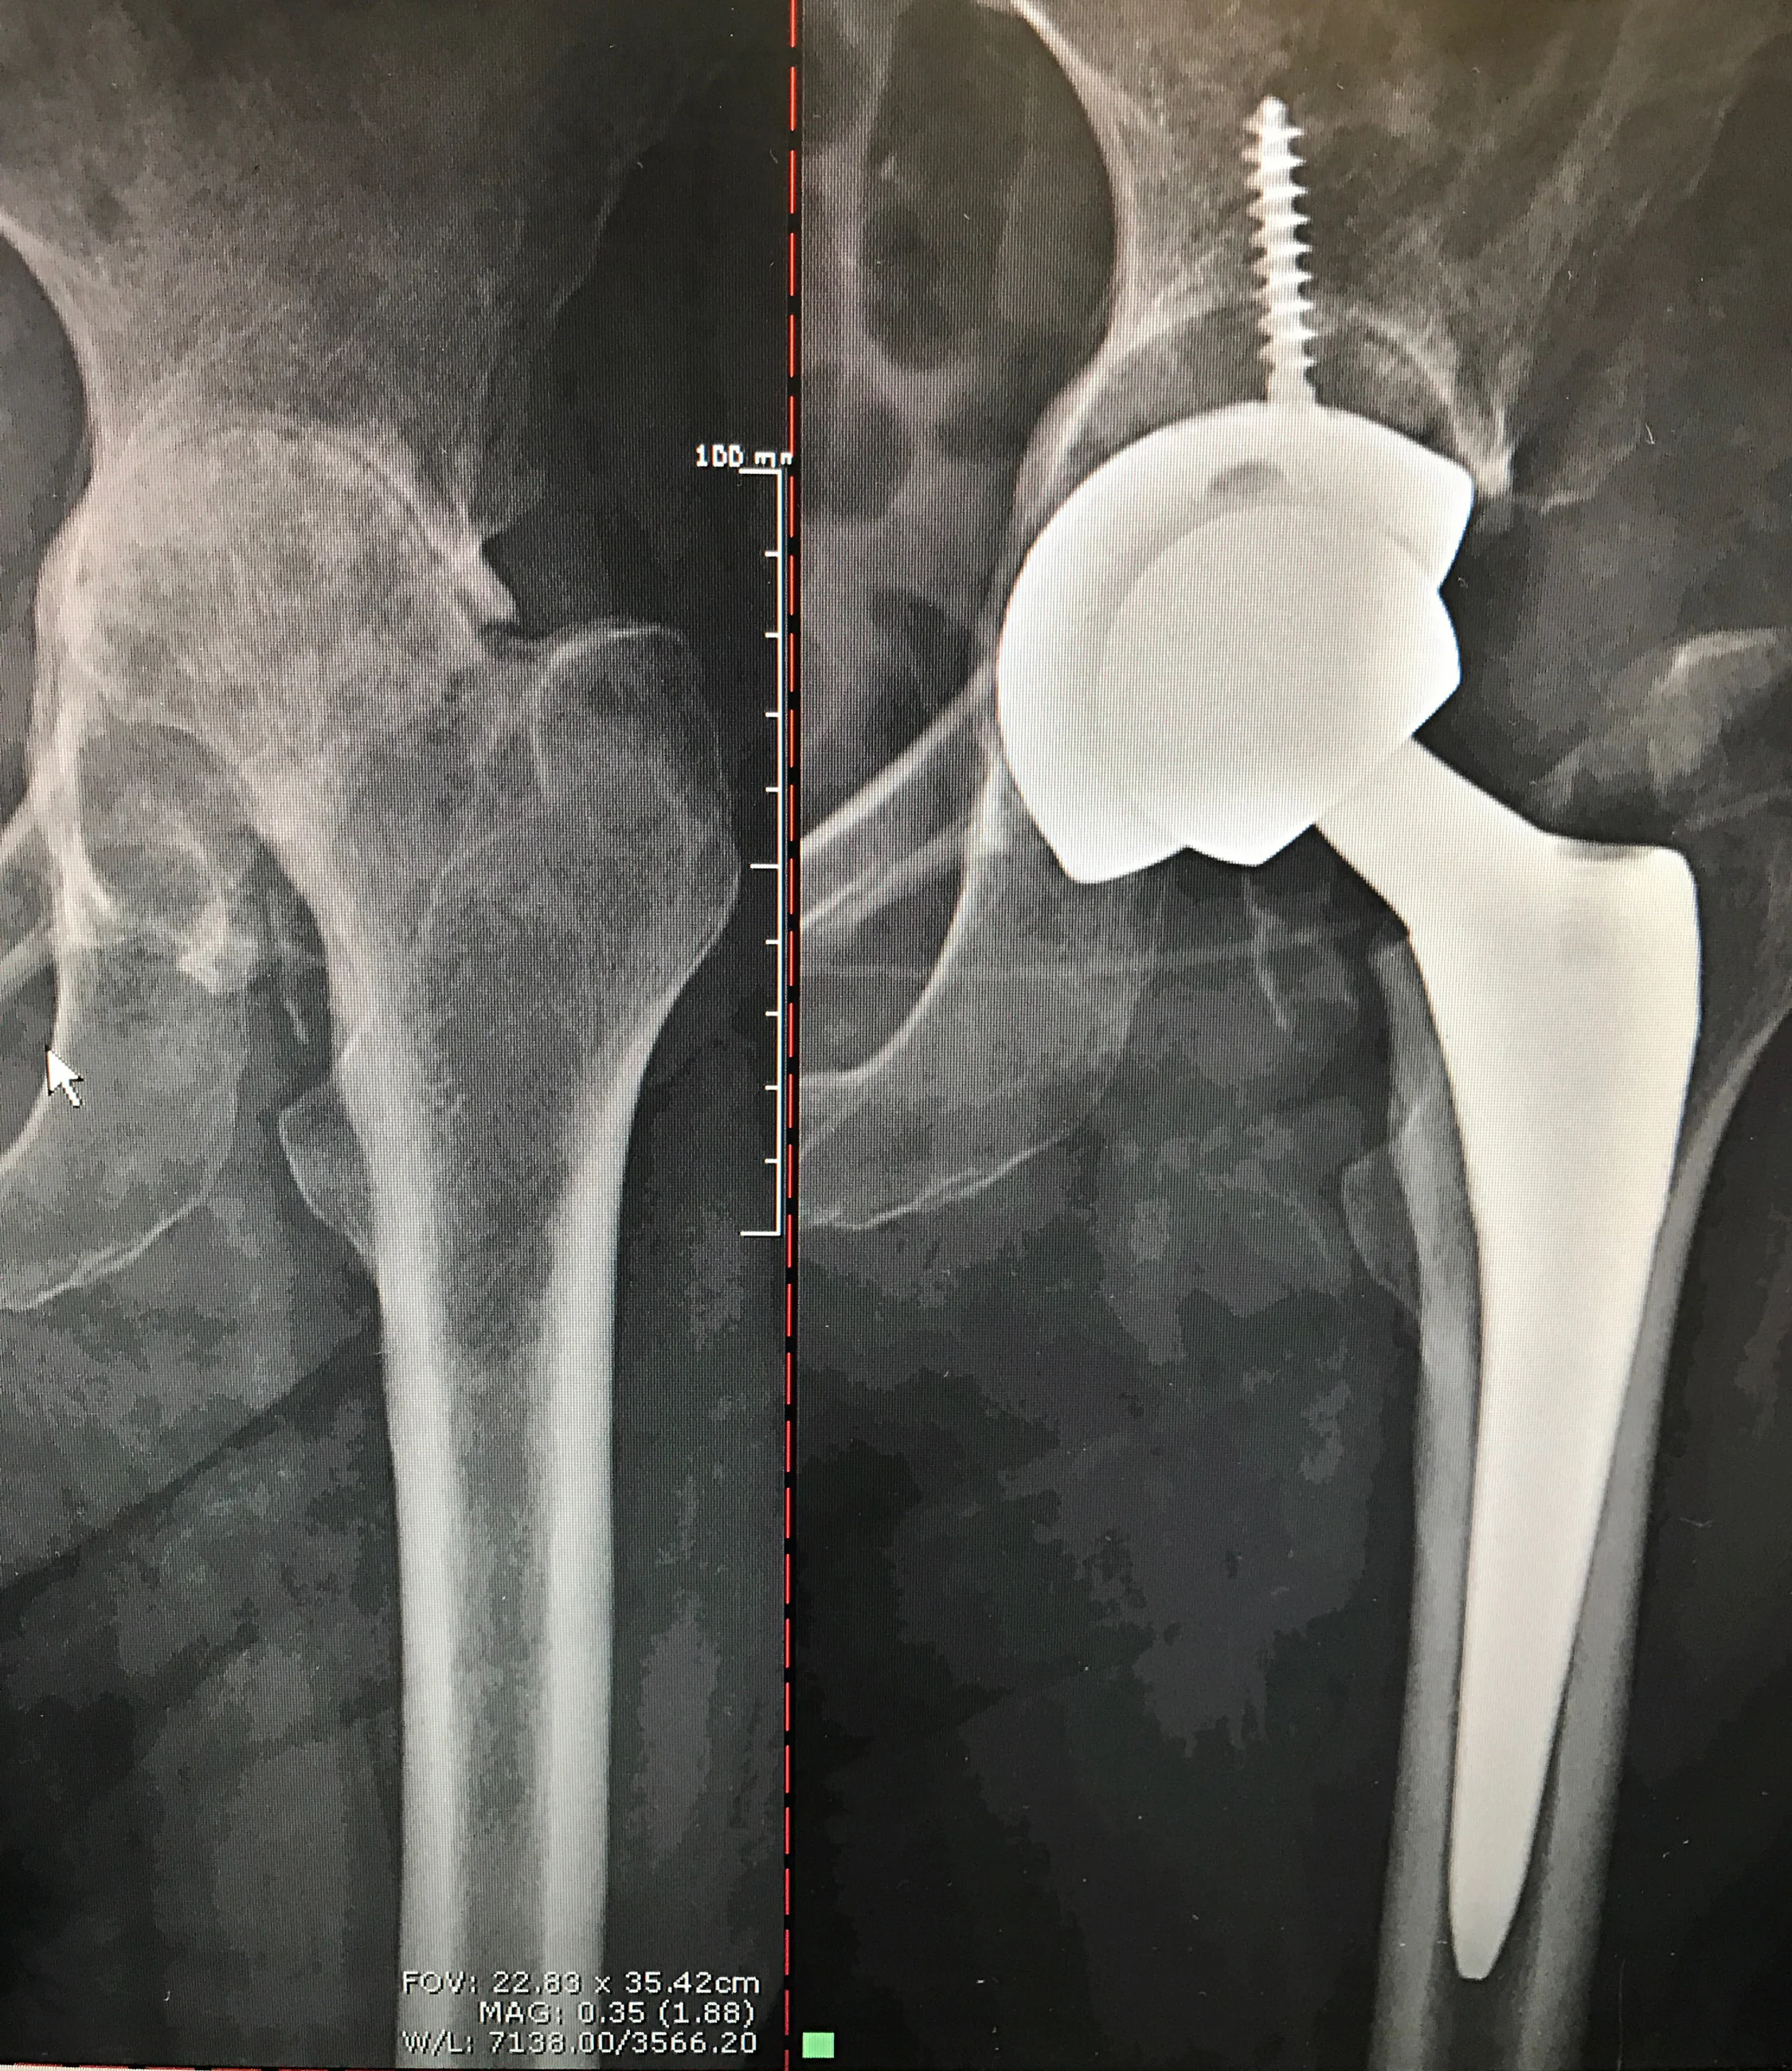

Before: Right-Femoral Head eroded up into Pelvis

After: Total Hip Replacement with Bone Graft from Femoral Head to fill the defect

OMNI